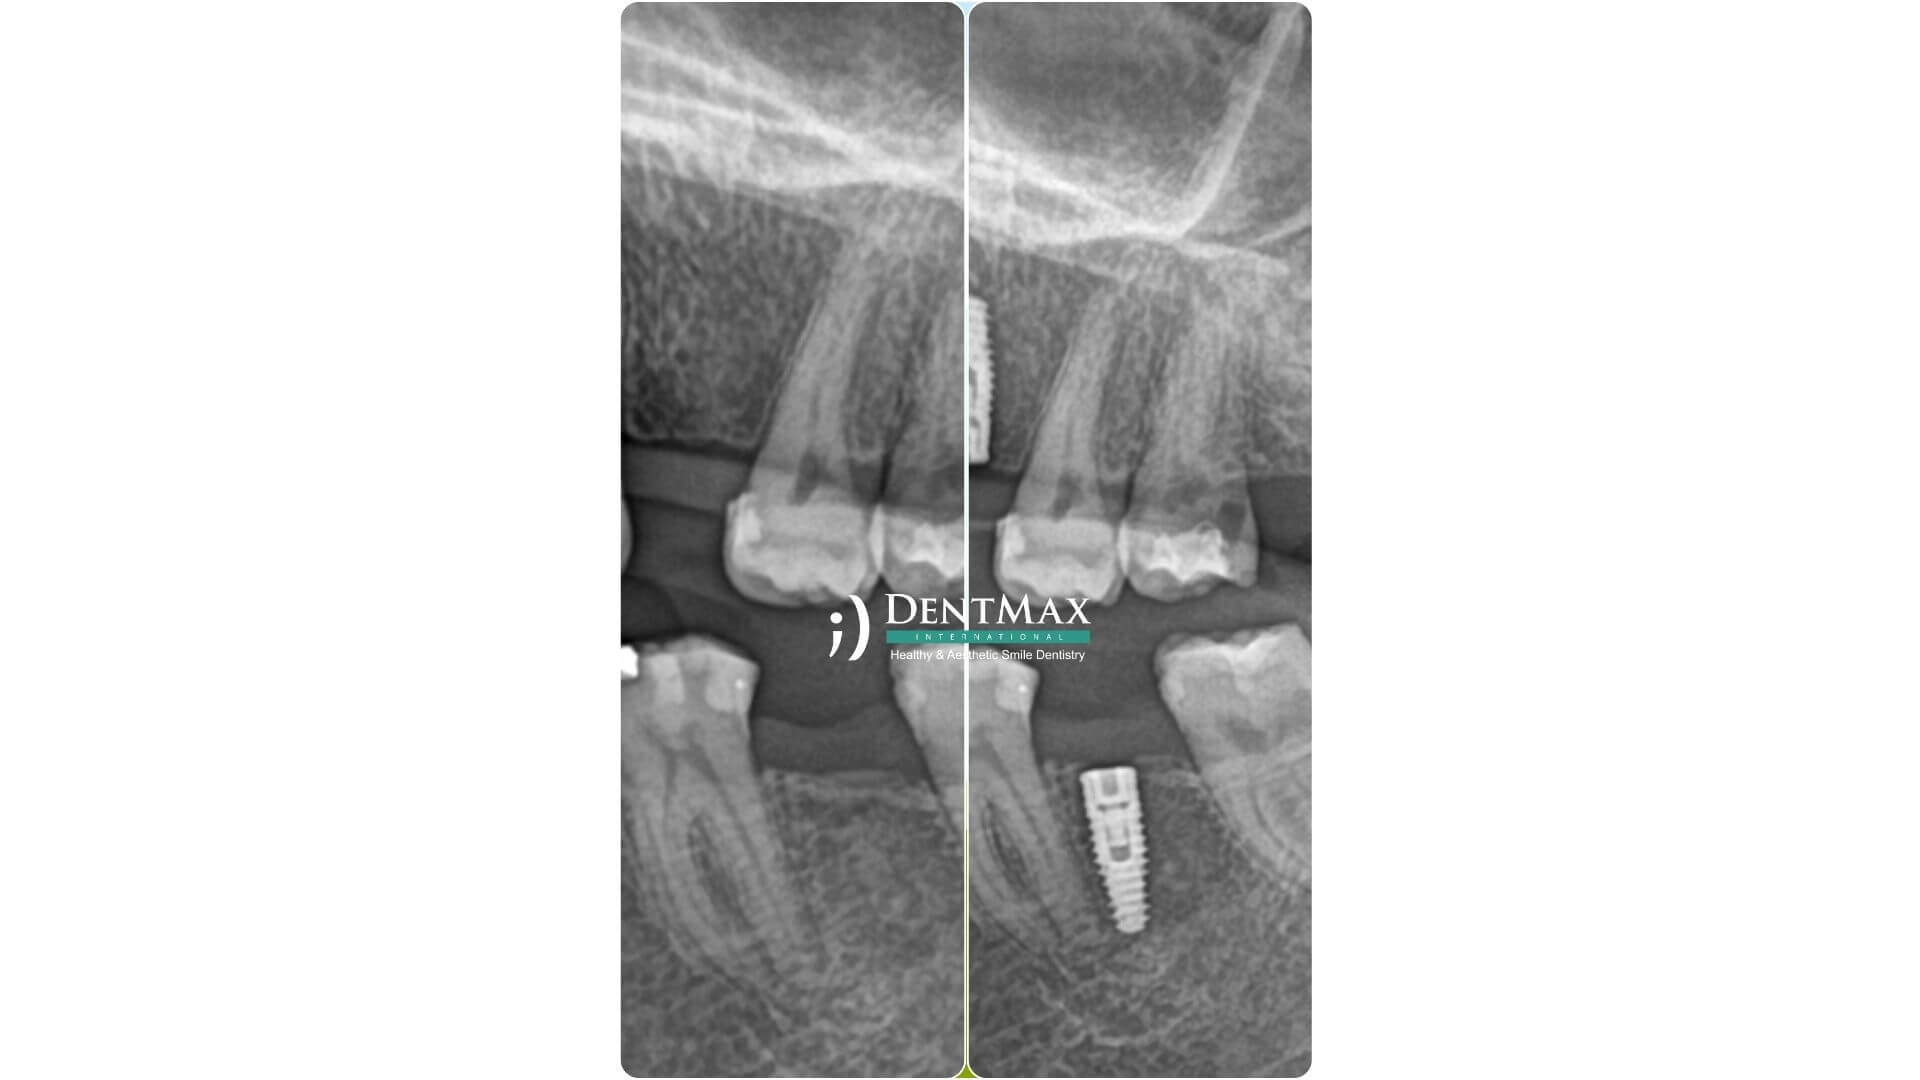

Çoklu implant - Köprüler

Ağızda birden fazla diş eksikliği olduğunda, her diş için ayrı implant yerine az sayıda implant üzerine sabit köprü yapılması işlemidir.

Gerekli görüntülemeler sonrası implantlar yerleştirilir. İyileşme sürecinden sonra sabit köprü protez implantlara vidalanır ya da yapıştırılır.

DentMax, dijital planlama, 3D rehberleme ve estetik diş protezleriyle çoklu diş eksikliklerine kalıcı çözümler sunar.